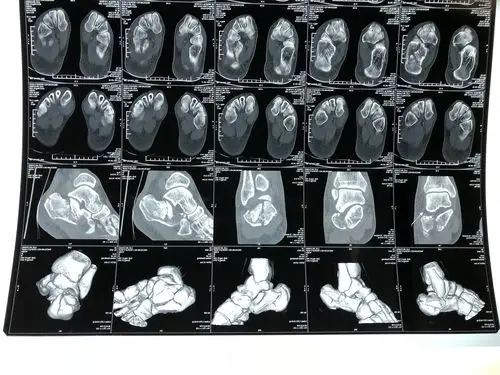

跟骨骨折微创手术,拒绝大切口,恢复快,功能好.#骨科 #微创 - 抖音

病人术前x线片:跟骨粉碎性骨折术中,4厘米小切口,损伤小,效果好术后

跟骨骨折追求的治疗目标:皮瓣安全,恢复跟骨高度,宽度,纠正内翻,恢复